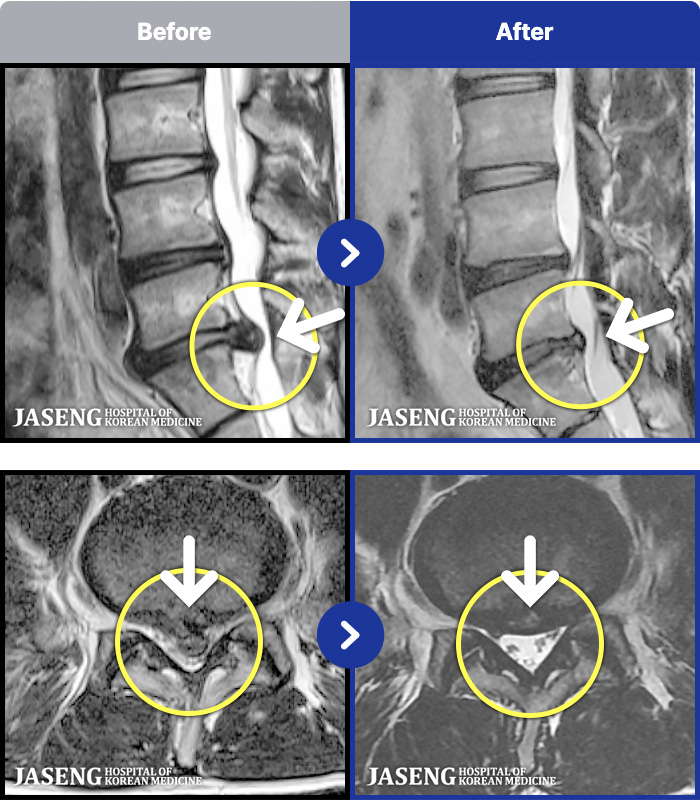

MRI ġ

54 MRI ũ ʸ Ȯϼ.

[Կñ:25.03.29~25.07.17]

[_㸮ũ] 㸮